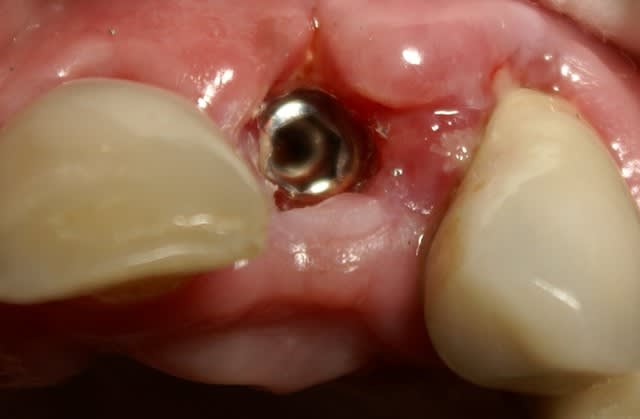

Dans ce cas là, c'était une implantation post extractionnelle immédiate et une mise en esthétique immediate.

Pour ceramik, l'implant est un Xive 3.8 dans le premier cas et un 3.4 dans le second (peut être un peu sous-dimentionné d'ailleurs).

Excellente stabilité primaire avec ces implants que je préfère aux straumann, easy et ankylos.

Tout à fait d'accord growler et c'est d'ailleurs ce que l'on peut voir sur le cas suivant. Fracture radiculaire, aucune infection periradicualire. Extraction et implantation immediate. Espace existant entre l'implant et l'alvéole est comblé par du BioOss. Un logement sous gingival est formé en vestibulaire et palatin de facon à pouvoir recouvrir le tout par BioGide et un conjonctif enfoui.

L'implant est de 15mm mais l'alvéole était large et 50% environ de la surface implantaire n'était en contact qu'avec du BioOss. J'ai pour cela préféré enfouir.